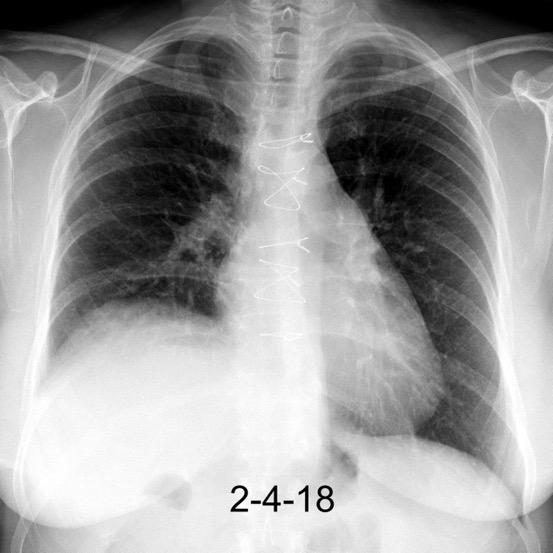

Síntomas y signos que se producen con la obstrucción total o parcial de la vena cava superior

Causas Malignas +/- 90-95%

Ca. Broncogénico (80-85%)

Linfoma No Hodgkin (15%)

Catéteres, shunts y marcapasos…23%

T. Mediastínico. Bocio

Fibrosis Idiopática

Tb, Histoplasmosis, Actinomicosis, Sarcoidosis

Carcinoma microcítico con síndrome de VCS